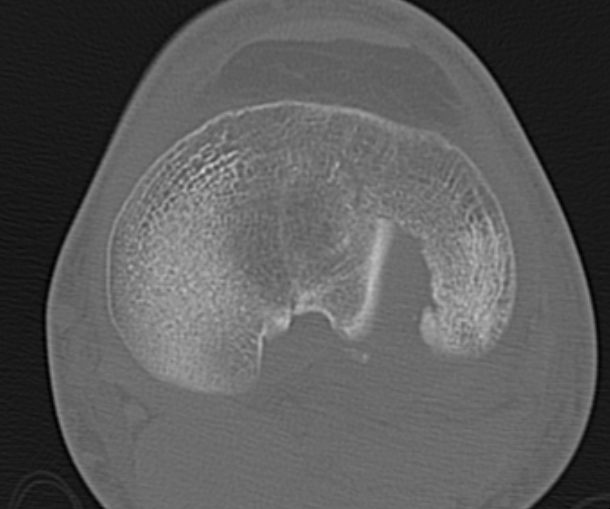

CT scan

Assess joint line

- predetermine fracture pattern before fixation

- will pick up medial condyle / bicondyle / metaphyseal fractures not seen on xray